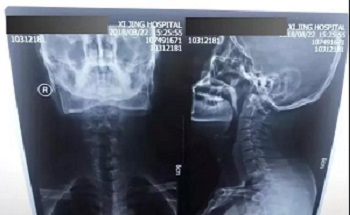

三、白天拍摄,窗户外光亮,室内关灯。

八、拍片子时,如果一张片子上有两张图像的时候,合起来拍一张,分开再各拍一张(如以下三张)